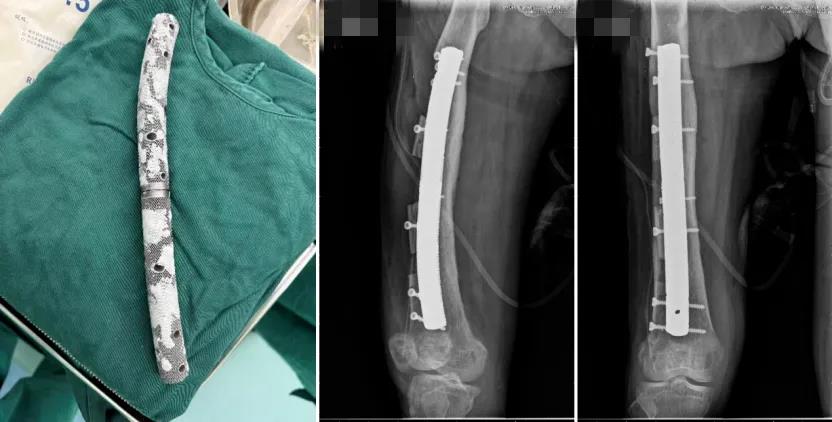

术后,宁女士接受了系统的营养支持与抗感染治疗。两周后,她的血红蛋白、白蛋白、C反应蛋白等指标显著改善,血小板也趋于正常。时机成熟!团队立即为其实施第二阶段手术——右股骨远端切开清创、病灶彻底切除,并植入个性化3D打印多孔钽载药人工骨假体。

手术室内,假体与骨床严丝合缝,宛如“量身定制的生命支架”。术中X光确认位置完美,符合术前数字模型预期。更令人振奋的是,术后仅两天,宁女士便能在助行器辅助下下地行走,并配合CPM机开始膝关节功能锻炼。这一速度,远超传统骨髓炎术后康复周期。

假体实物图及术后复查DR